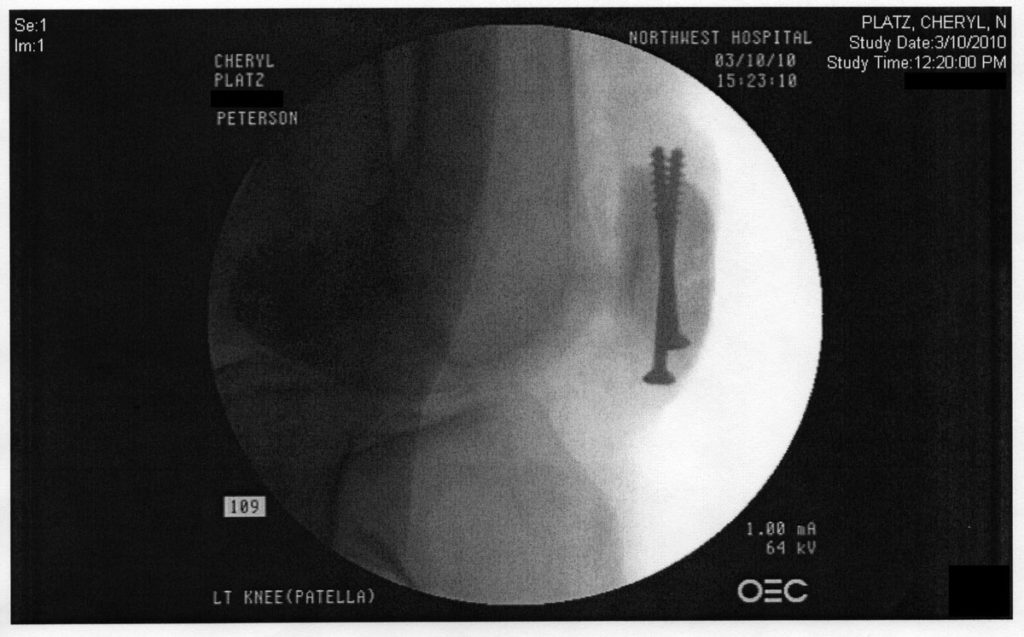

The injury was catastrophic and instantaneous. One moment I was walking, the next minute I was in unimaginable pain on the ground, screaming like a banshee. My brain literally reasoned that all of the planets in the universe must have converged on my kneecap at once to cause such a sensation. I don’t recommend it. Also, I was completely unable to move my leg, it was frozen in place. Which led to this before and after:

None of those things was without pain, however. Keeping my leg bent for more than 30 minutes – like on a plane, or even at a meeting – was painful. My knee was hot to the touch. Not infected, just permanently overheated, even through heavy fabric. If someone made the mistake of touching my knee, jangled nerve endings would give me horrible flashbacks. I limped every now and again. I was icing most nights, especially during shows. But worst of all, I could feel the points of the screws. It was unavoidable, but it was truth.

My friends who had the similar misfortune of hardware implants recommended I get them removed as soon as possible, so about 14 months later I went back in under my own power and had the screws taken out (Which I wrote about in this post from 2011). Naturally, 6 weeks later I performed in the debut of our Star Trek improv show, a show with fight choreography and a bit of risk.